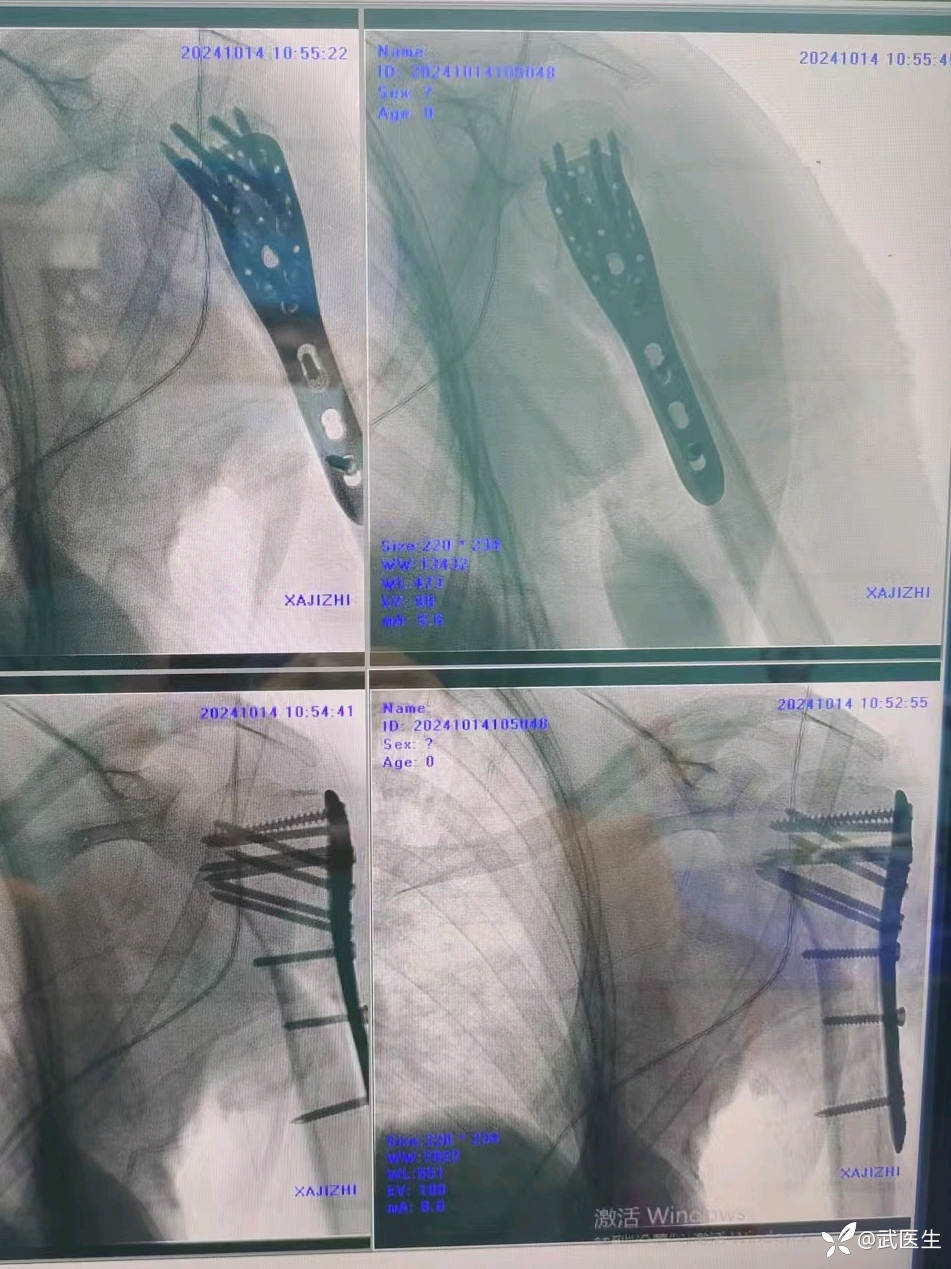

【治疗经过及结果】:入院完善检查,择期安排手术。患者年轻,肱骨外科颈骨折选择保头治疗。择期安排。

术中透视复位良好,术后CT验证一下